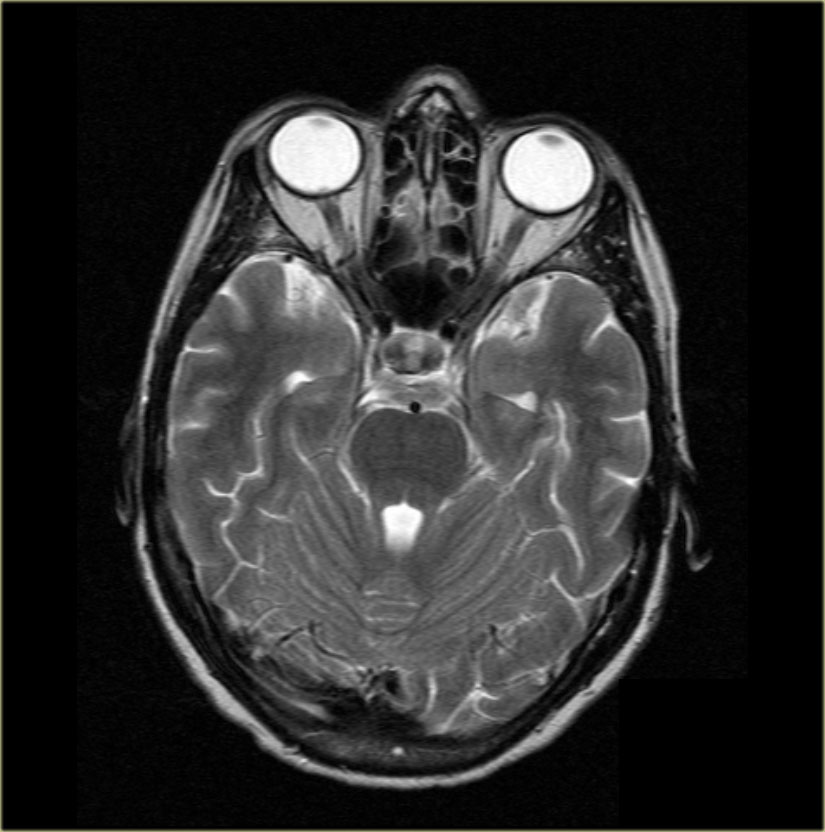

Giải phẫu trên mặt phẳng cắt ngang (Axial)